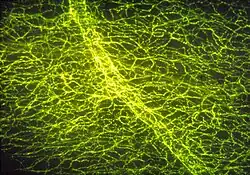

The next step led to the central nervous system. It was taken by Marthe Vogt, a refugee from Germany who at that time worked with John Henry Gaddum in the Institute of Pharmacology of the University of Edinburgh. "The presence of noradrenaline and adrenaline in the brain has been demonstrated by von Euler (1946) and Holtz (1950). These substances were supposed, undoubtedly correctly, to occur in the cerebral vasomotor nerves. The present work is concerned with the question whether these sympathomimetic amines, besides their role as transmitters at vasomotor endings, play a part in the function of the central nervous tissue itself. In this paper, these amines will be referred to as sympathin, since they were found invariably to occur together, with noradrenaline representing the major component, as is characteristic for the transmitter of the peripheral sympathetic system."[51] Vogt created a detailed map of noradrenaline in the dog brain. Its uneven distribution, not reflecting the distribution of vasomotor nerves, and its persistence after removal of the superior cervical ganglia made it "tempting to assign to the cerebral sympathin a transmitter role like that which we assign to the sympathin found in the sympathetic ganglia and their postganglionic fibers." Her assignment was confirmed, the finishing touch being the visualization of the noradrenaline as well as adrenaline and dopamine pathways in the central nervous system by Annica Dahlström and Kjell Fuxe with the formaldehyde fluorescence method developed by Nils-Åke Hillarp (1916–1965) and Bengt Falck (born 1927) in Sweden and by immunochemistry techniques.[52]